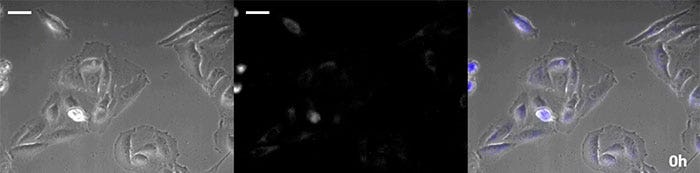

【明視野画像】

【発光画像】

【重ね合わせ画像】

発光画像疑似カラー(緑)

動画1. ヒスタミン刺激によるカルシウムイオン変動の化学発光観察(スケールバー500µm)

薬効評価を行う上で細胞の経時的な観察は、その影響を詳細に解析するために必要となります。以前より化学発光はルシフェラーゼの成熟時間と半減期が短い特性より、遺伝子発現のレポーターとしてその経時変化を解析することに適すことが知られています。また、蛍光と異なり励起光が不要なため、長時間のイメージングに用いる場合には、細胞に対する光毒性は軽減されます。ただし、化学発光は発光基質 (ルシフェリン) を必要とするため、細胞へのルシフェリンの安定供給が重要です。特に、セレンテラジン (Coelenterazine) 系のルシフェリンは高光度で発光しますが、培地中で短時間に酸化されやすいため、長時間観察を行う場合には適時添加することが必要となります。そこで、高光度化学発光タンパク質を導入した細胞に自動基質添加・培地灌流装置を用いてセレンテラジンを自動添加しながら培地灌流をし、化学発光を経時的に観察した結果、位相差画像と併せて化学発光画像を24時間以上連続して観察することに成功しました(図4)。

0時間後

図4-1 0時間後

6時間後

図4-2 6時間後